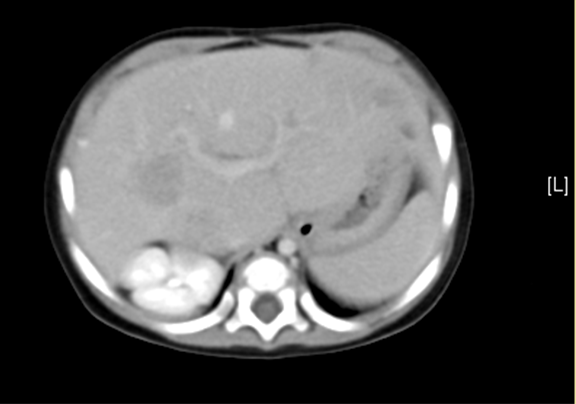

平衡期

随访3天,肝脏术后所见,双侧胸腔积液。